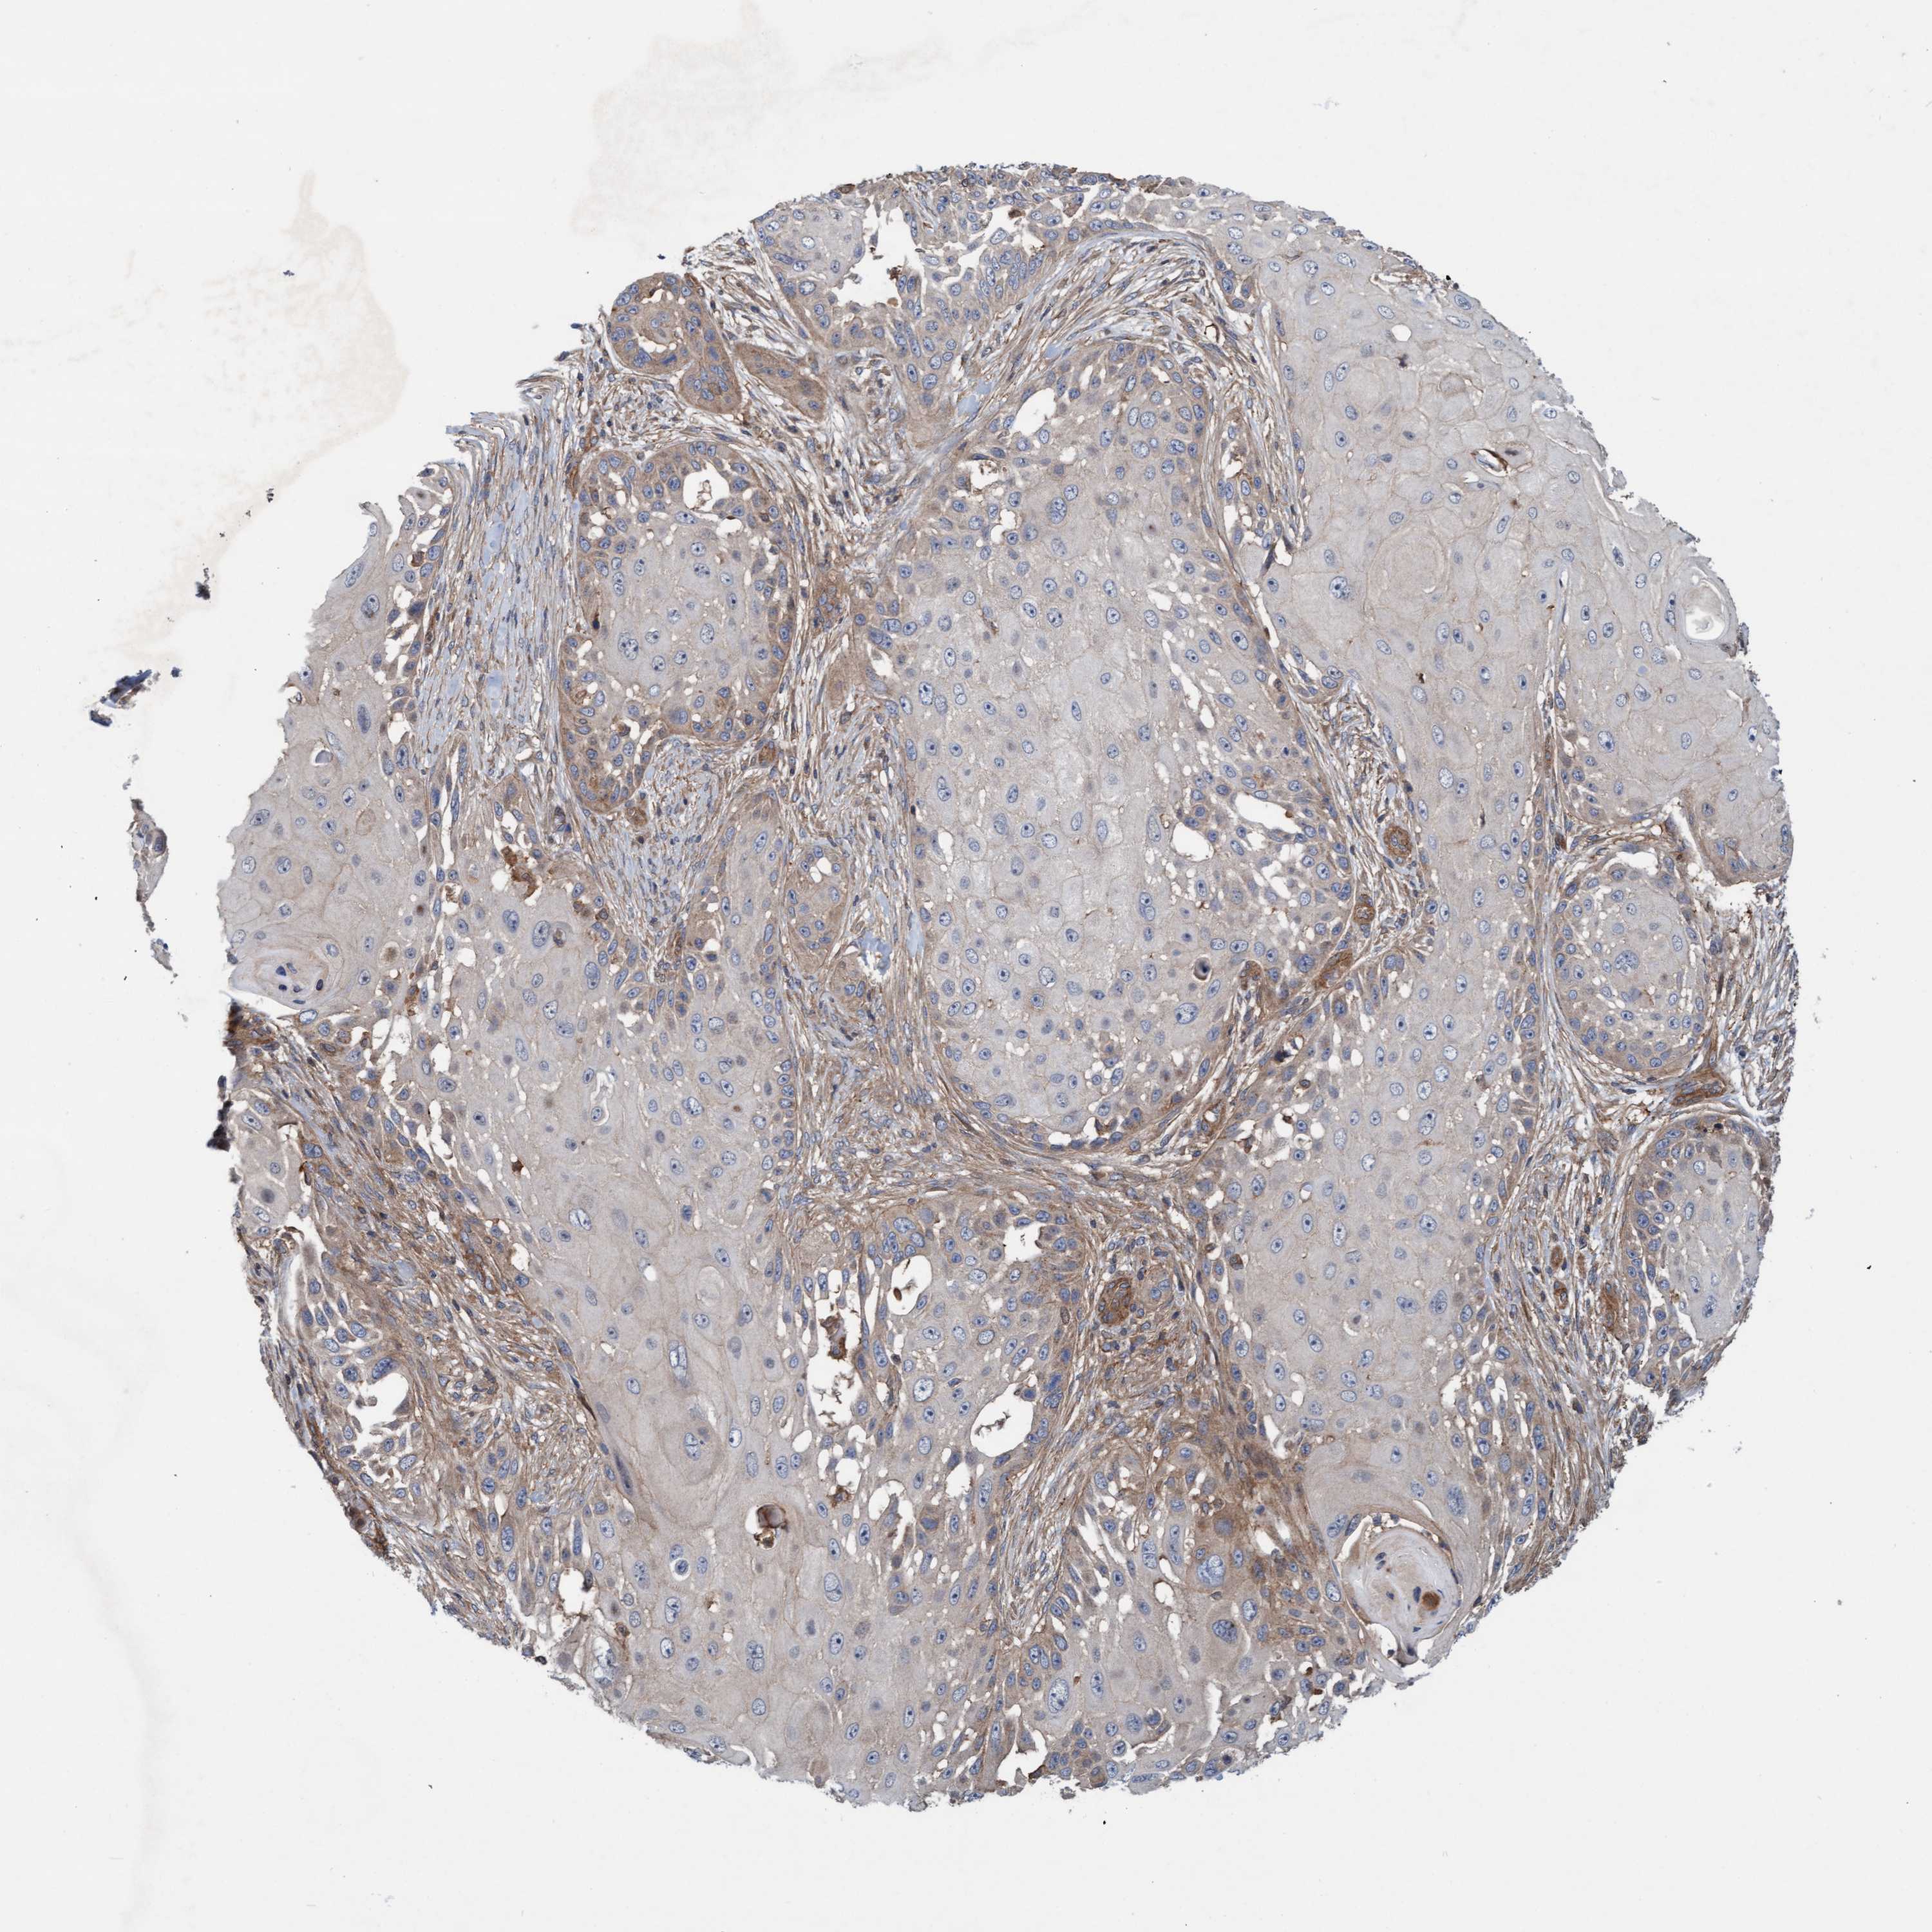

CANCER SKIN CANCER Show tissue menu

Basal cell and squamous cell cancer

SKIN CANCER - Protein expressioni

A mouse-over function shows sample information and annotation data. Click on an image to view it in a full screen mode. Samples can be filtered based on level of antibody staining by selecting one or several of the following categories: high, medium, low and not detected. The assay and annotation is described here.

Each image is clickable and will lead to virtual microscopy that enables deeper exploration of all samples and also displays staining intensity scores, fraction scores and subcellular localization as well as patient and tissue information for each sample.

Antibody HPA021425

Basal cell carcinoma

Squamous cell carcinoma, NOS

Squamous cell carcinoma, metastatic, NOS